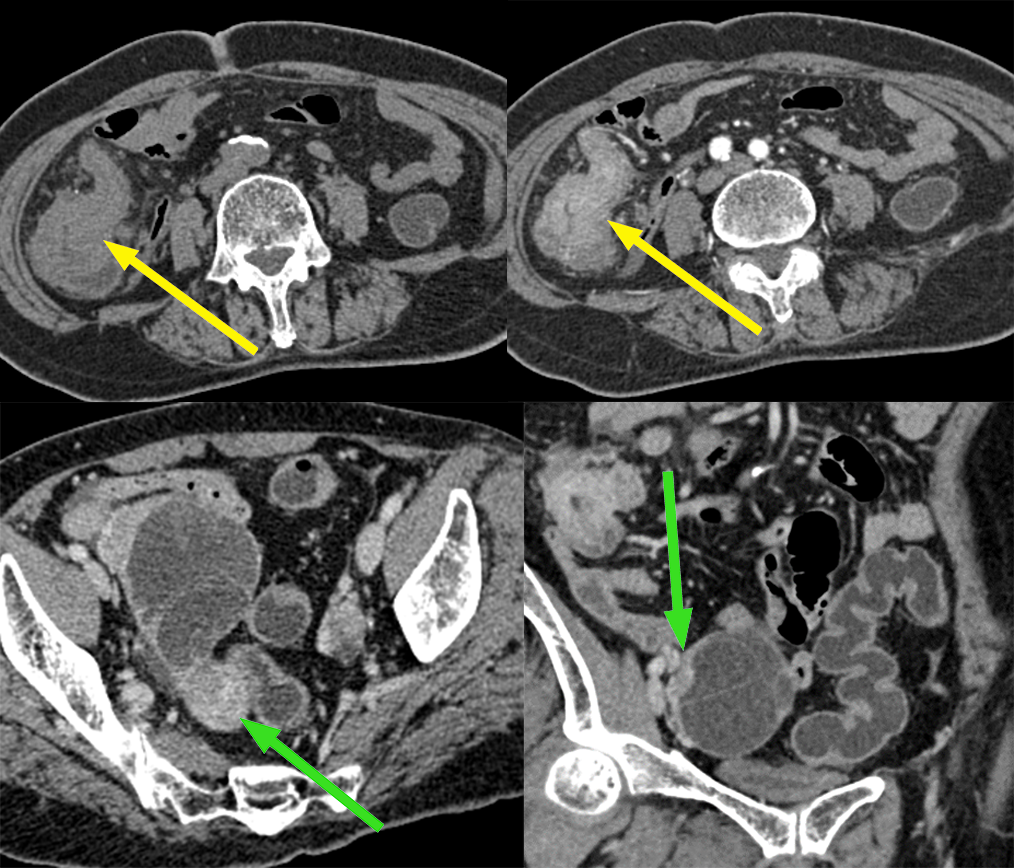

患者,女,70 岁,因排便习惯改变 1 年入院,肠镜及病理:升结肠近回盲部中低分化腺癌;CA125 正常。

影像描述:回盲部肠壁限局性环状增厚,突向腔内,表面不光滑,管腔明显变窄,浆膜层毛糙,增强呈明显不均匀强化,与肠壁边界不清,与周围组织分界尚清,周围脂肪间隙密度增高、浑浊,可见多个结节状软组织密度影,大小约 0.4-1.3 cm,明显强化。右侧附件区见较大囊实性团块影,其内可见分隔,大小约 6.7X5.5 cm,增强扫描实性部分及分隔可见明显强化,与邻近肠管及子宫体分界略欠清。

病例 2 手术:结肠癌合并卵巢转移癌

3、卵巢转移瘤 CT 表现:CT 是鉴别诊断的重要手段,双侧或单侧卵巢实性(乳腺癌,小)或囊实性(结肠癌,大)肿块,80% 的卵巢转移瘤为双侧生长,密度不均,大小不等,常有大量腹水和其他部位转移。

胃黏液腺癌双侧卵巢转移:双侧卵巢多房肿块